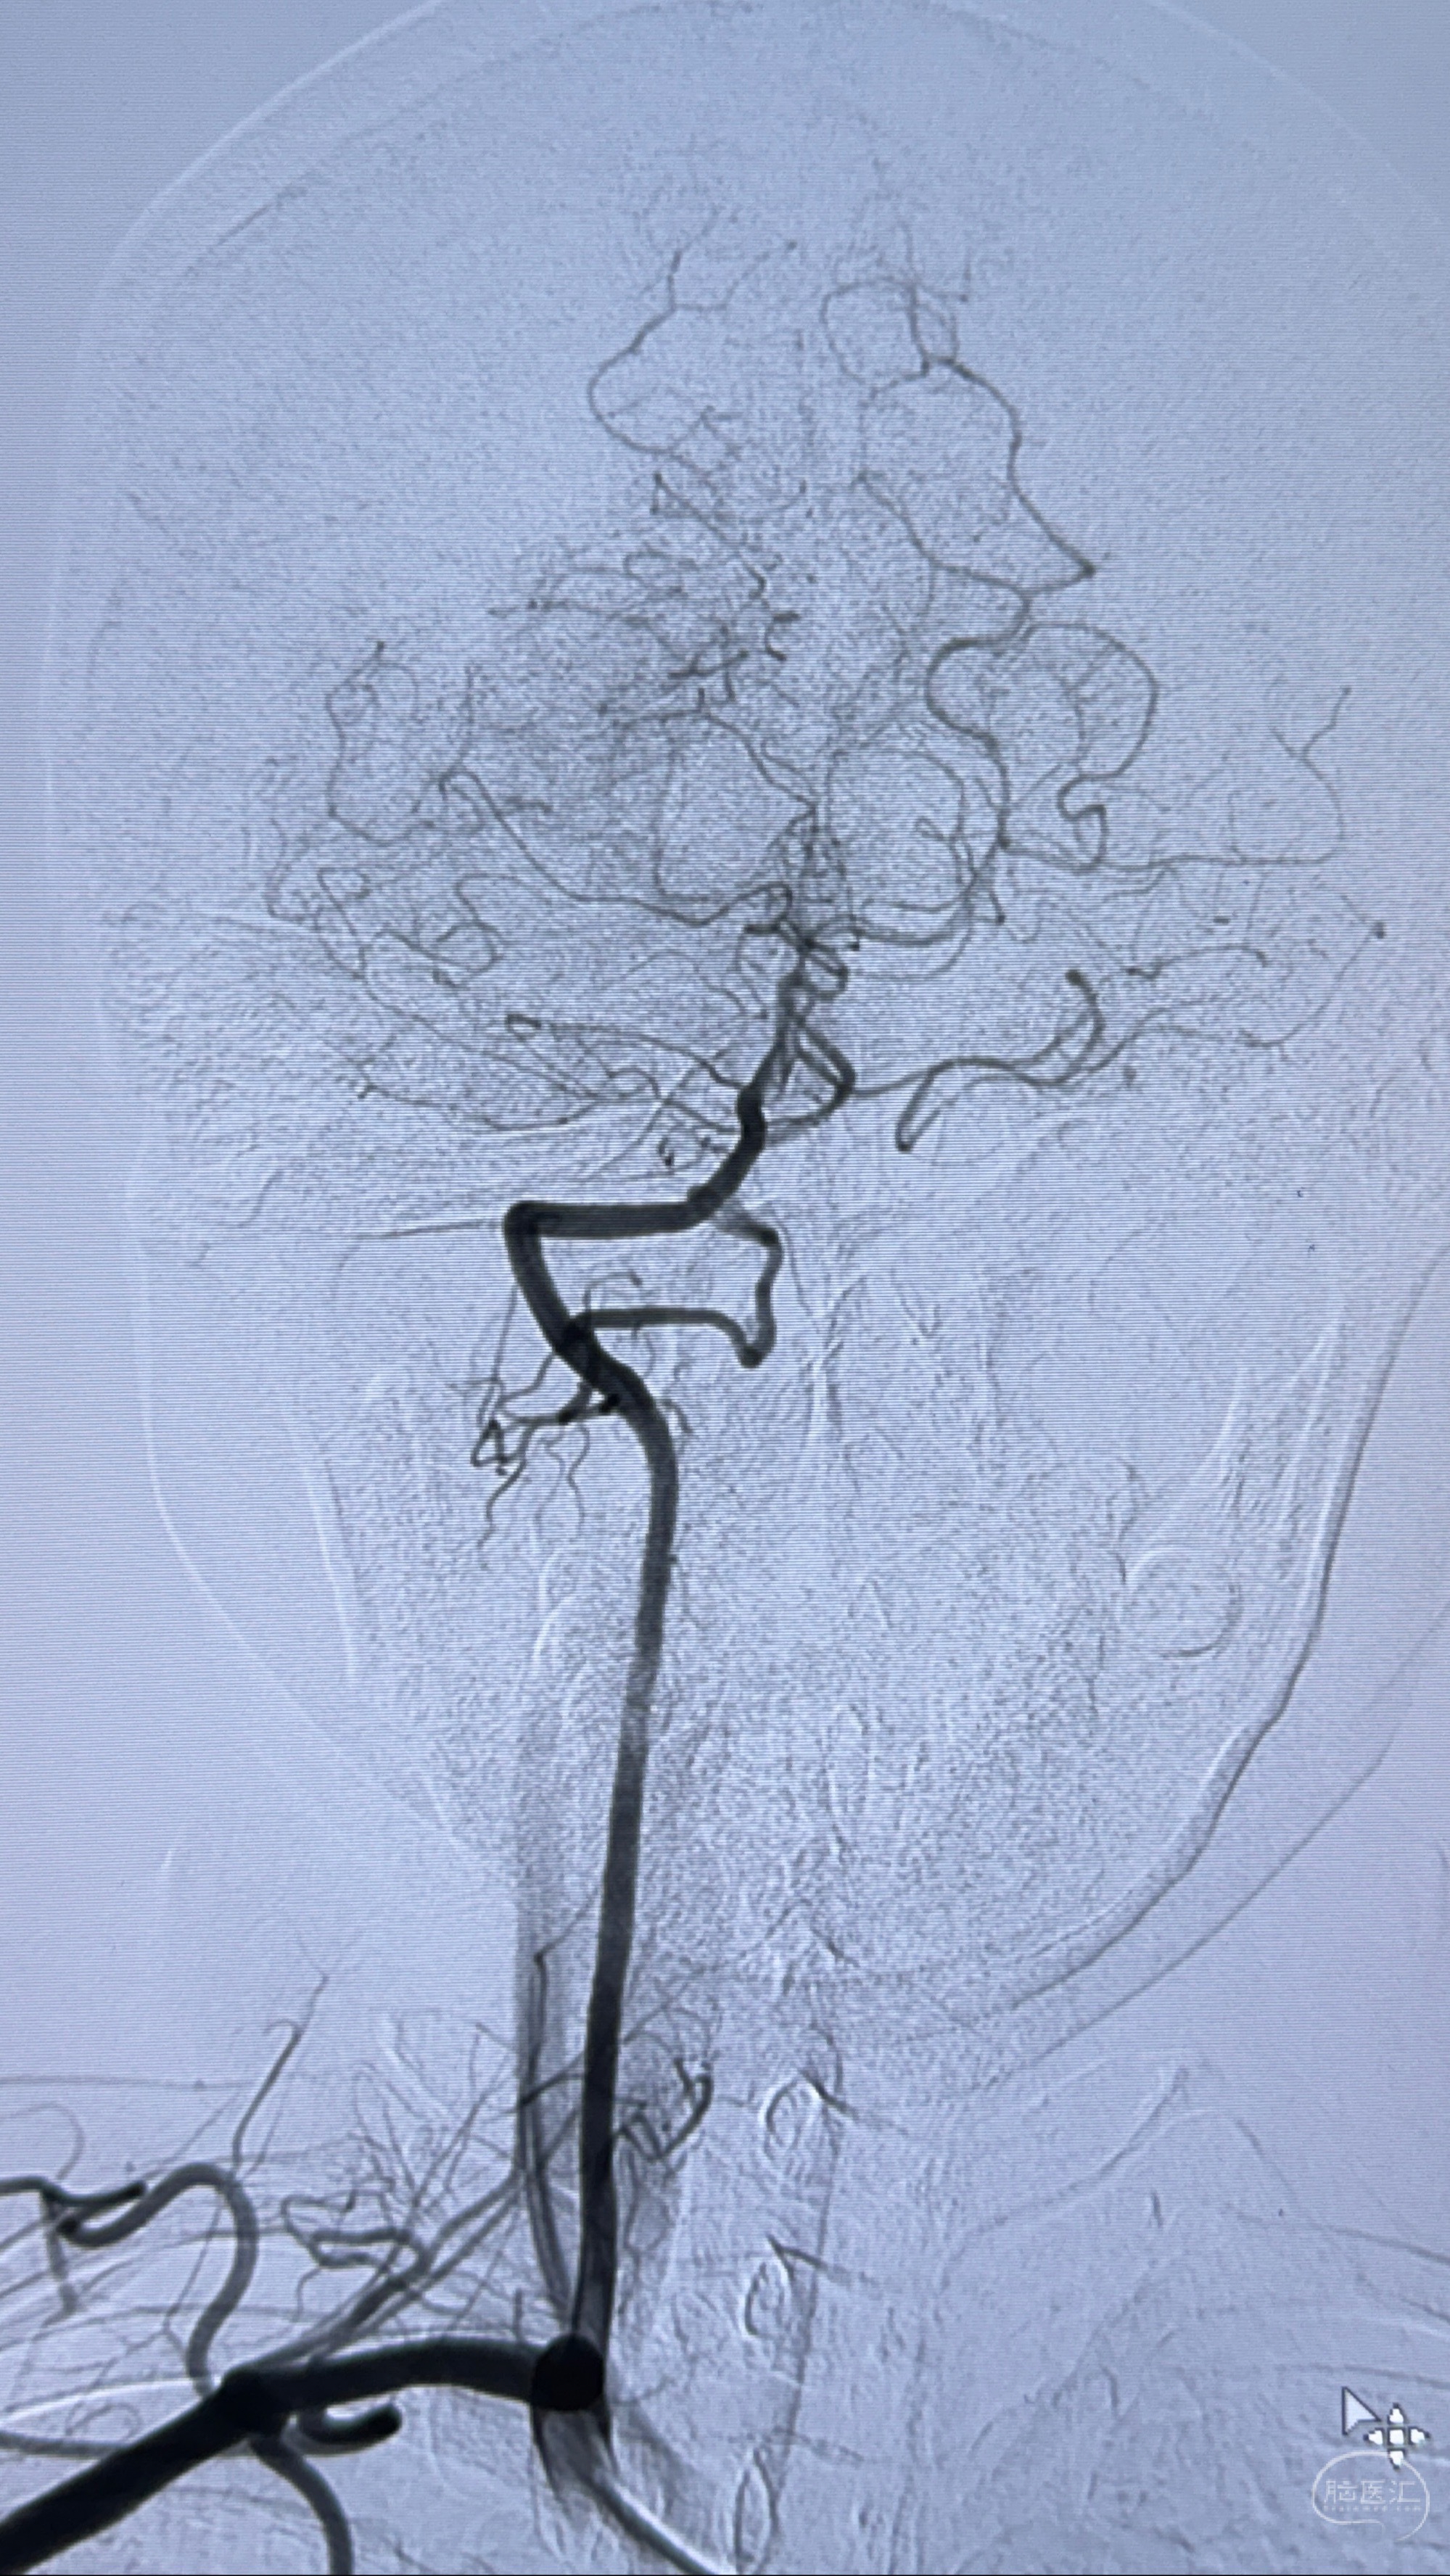

现病史:患者诉近4年来时有头痛发作,服用都梁软胶囊、氟桂利嗪对症治疗一月后症状改善,后头痛较少发作。近3月来患者头痛发作频率明显增加,约一月一次,为右侧偏头痛,胀痛,伴恶心呕吐,呕吐后症状可略减轻;遂于2023-11-01至蓝十字脑科医院就诊,查头颅MRI+DWI+MRA提示:左侧枕叶皮层下小斑片缺血或变性灶,右侧大脑前动脉A1段毛糙,显影淡、纤细,建议完善CTA;并于2023-11-03查头颅CTA提示:左侧颈内动脉C6段微小动脉瘤可能(约2mm),右侧大脑前动脉A1段纤细(对侧优势),左侧大脑中动脉提前分叉。现患者无明显不适,为求进一步诊疗颅内血管病变至我科就诊,收治入院。

2023-11-03 蓝十字脑科医院 头颅CTA:左侧颈内动脉C6段微小动脉瘤可能(约2mm),右侧大脑前动脉A1段纤细(对侧优势),左侧大脑中动脉提前分叉。

1.左侧颈内动脉瘤